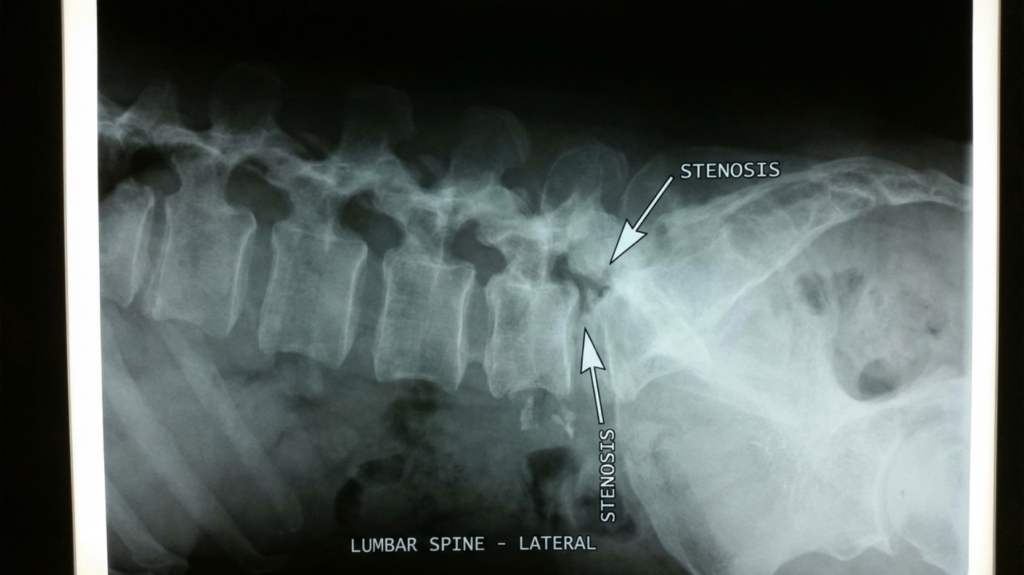

척추관협착증은 척추 안쪽의 신경 통로가 오랜 시간에 걸쳐 점점 좁아지면서 신경을 압박하는 퇴행성 질환이에요. 가장 특징적인 증상이 바로 ‘간헐적 파행’이에요.

다른 질환이에요. 디스크는 추간판이 튀어나와 신경을 누르는 거고, 협착증은 척추관 자체가 좁아져 신경을 압박하는 거예요. 증상이 비슷해 보여도 치료 방향이 달라질 수 있어서 정확한 MRI 진단이 필요해요.